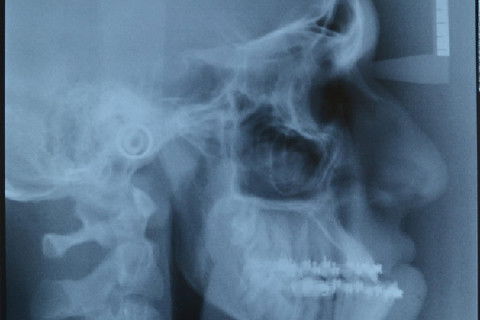

Telerradiografia de Perfil pré operatório